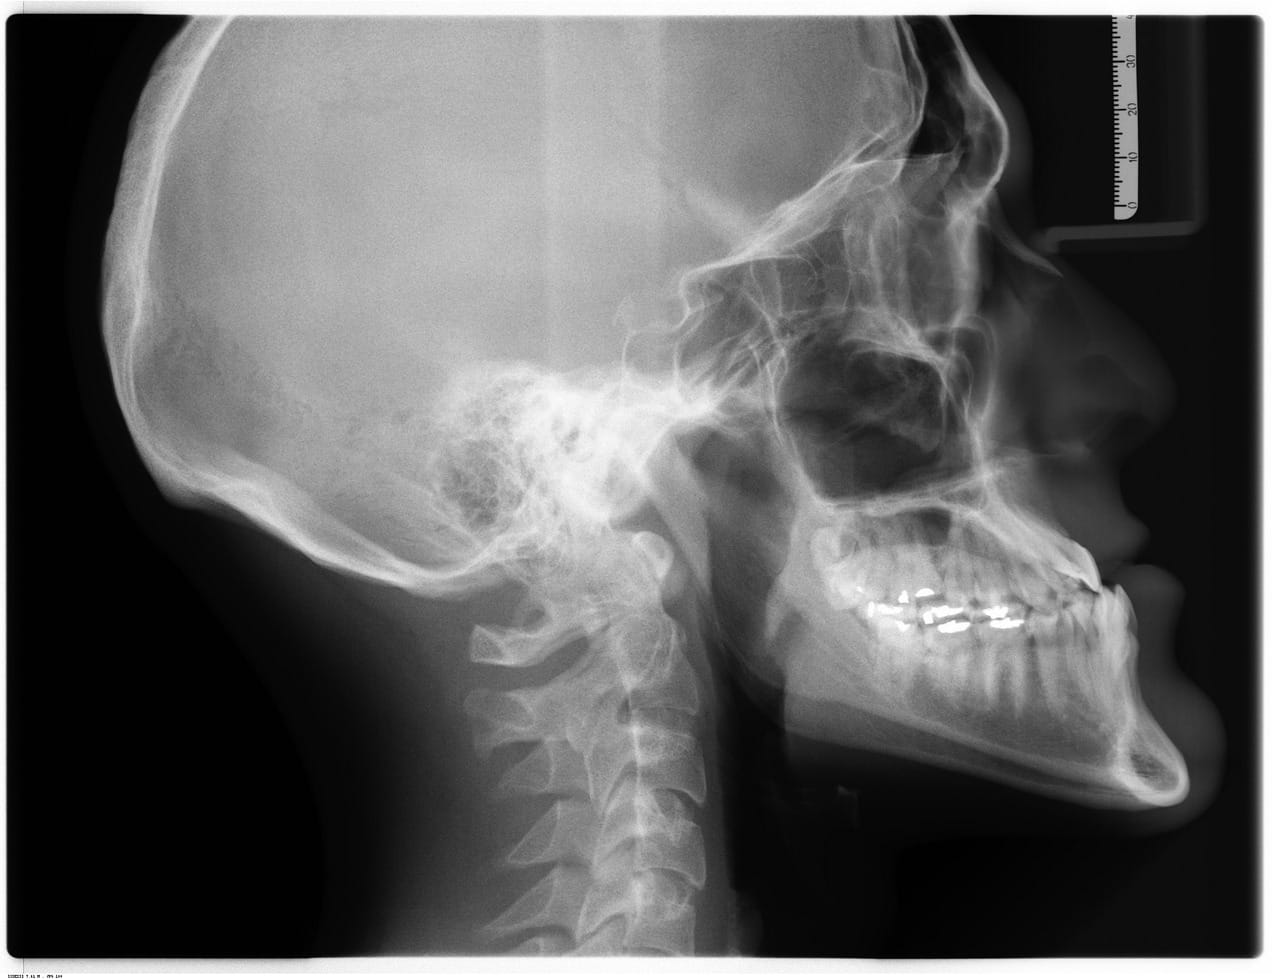

- Bildediagnostikk: MR, ultralyd og røntgen brukes ofte for å enten bekrefte eller utelukke mer alvorlige tilstander som brudd eller brokk.